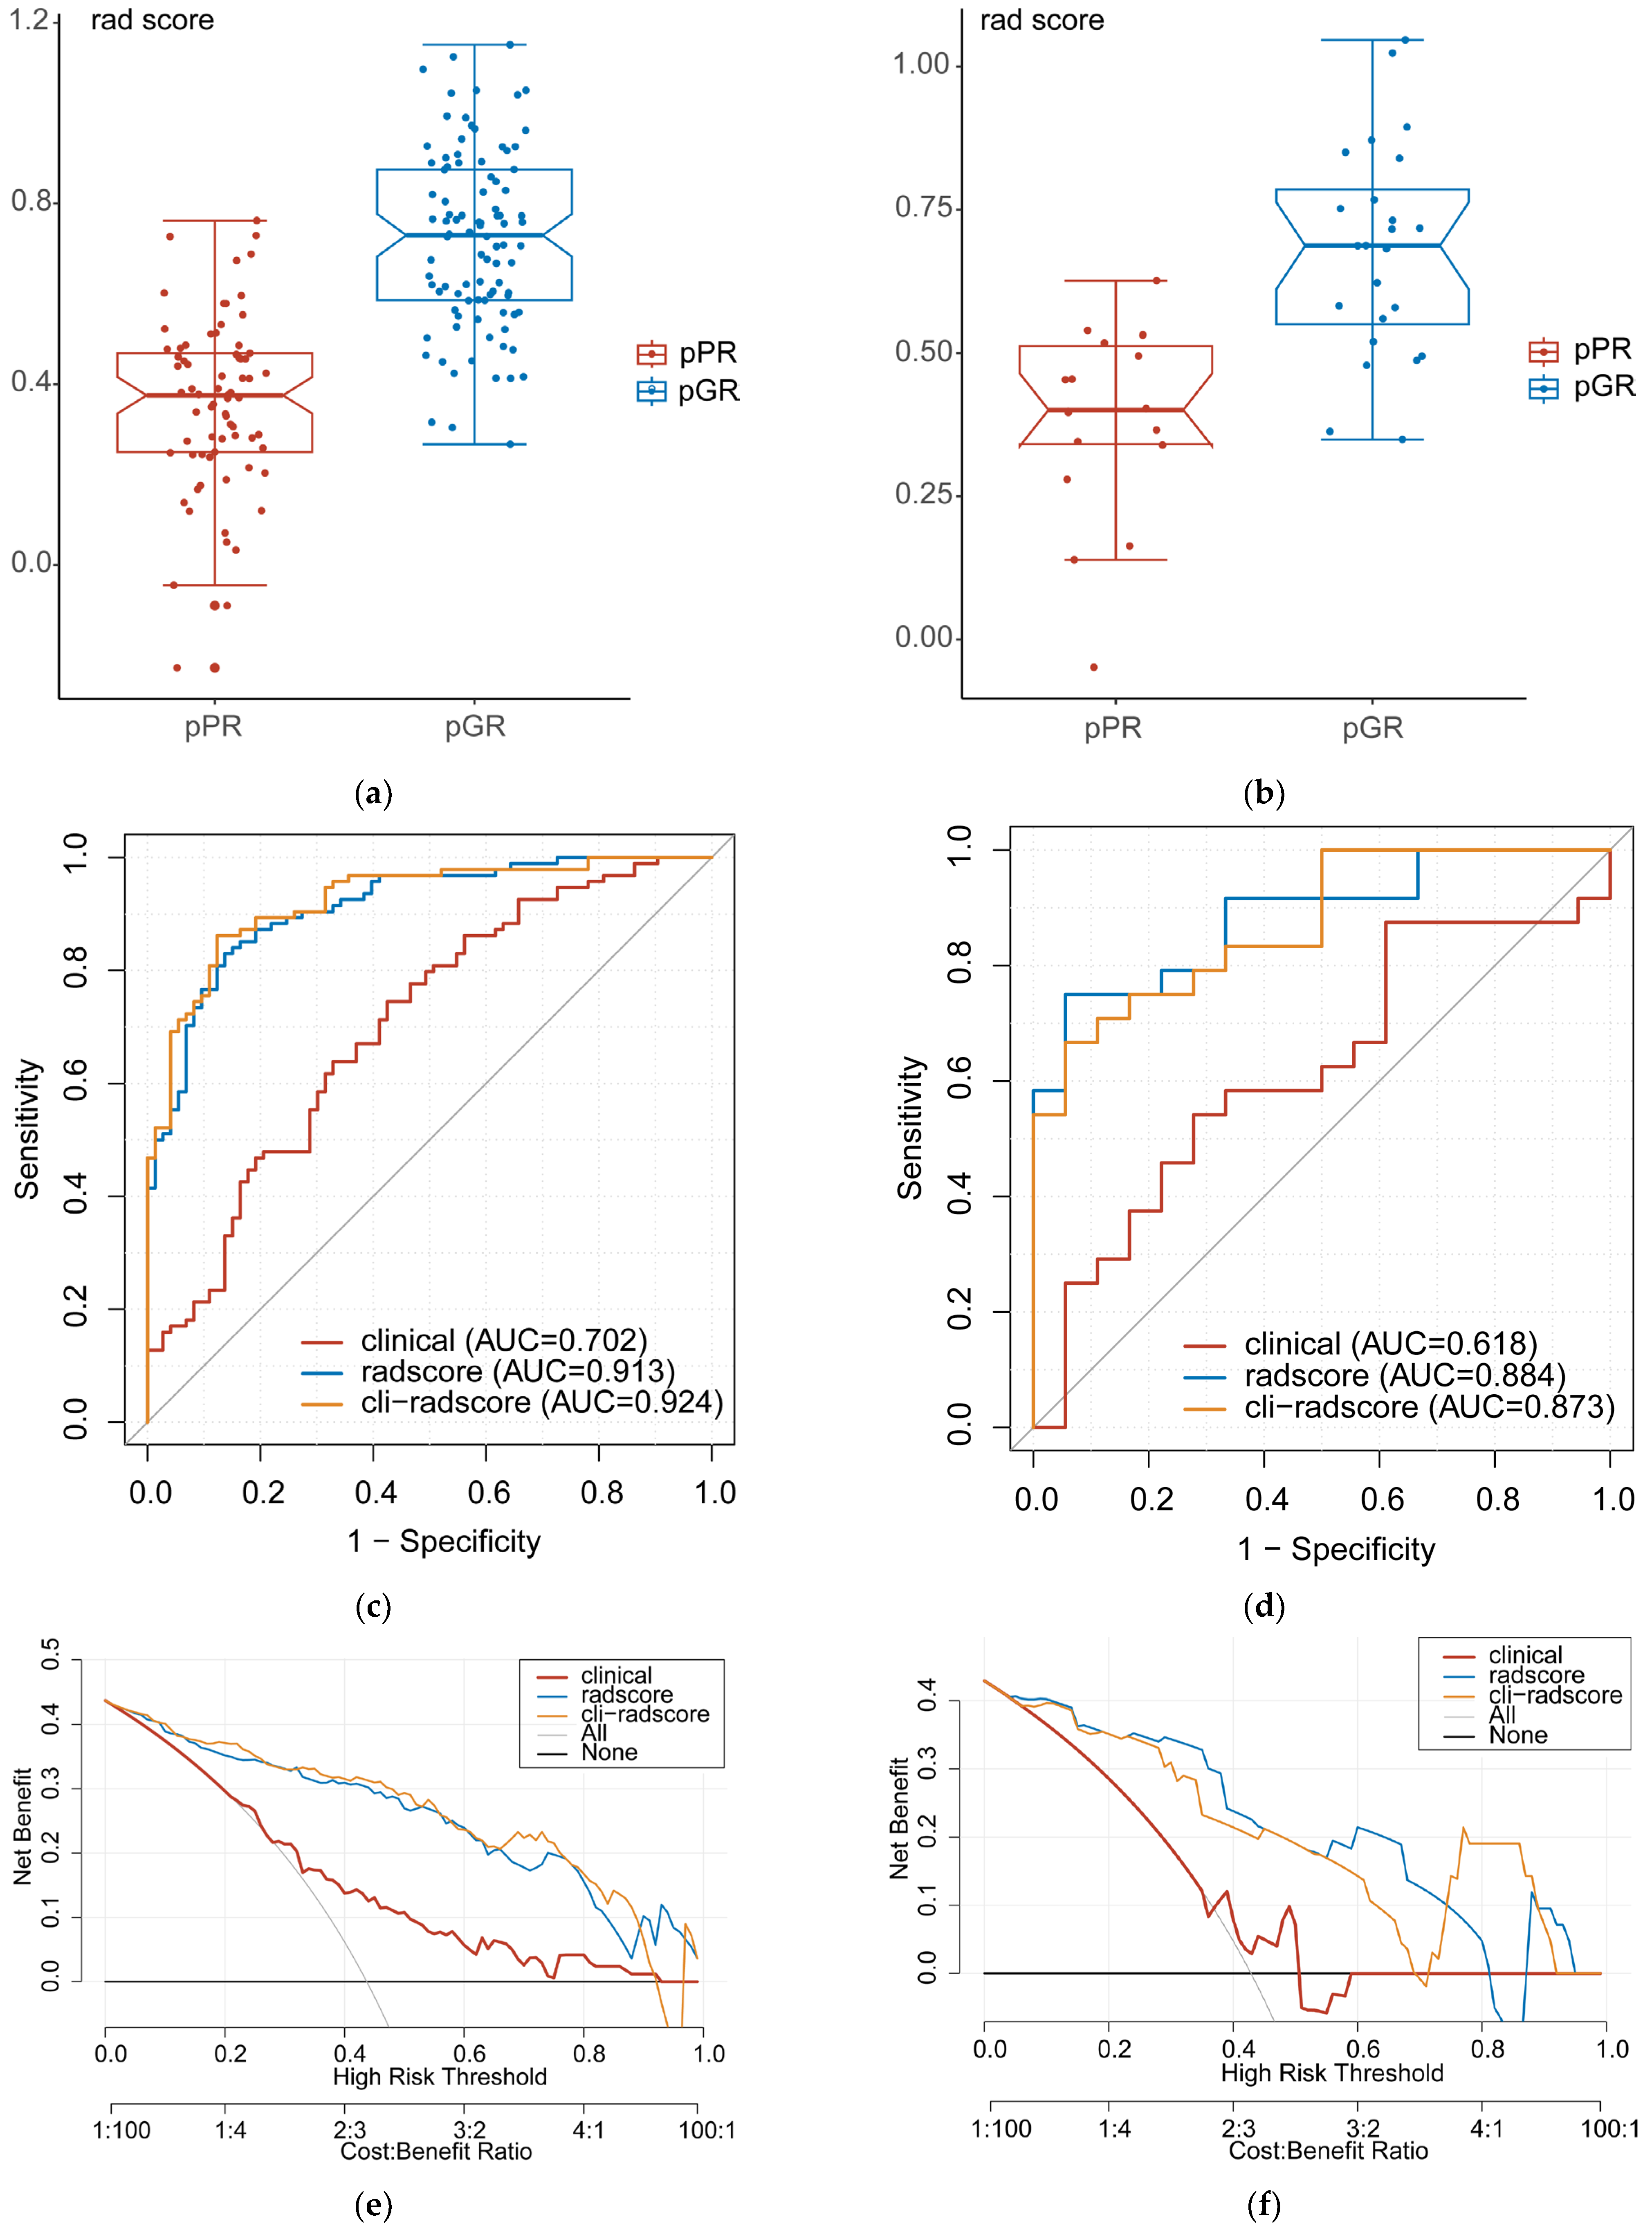

3.4. Clinical, Radscore, and Cli–Radscore Models

3.5. The Association between Radscore and Disease–Free Survival